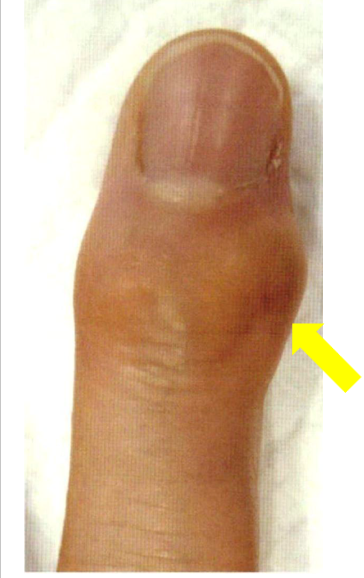

へバーデン結節

指の第一関節の軟骨のすり減り、変形によって第一関節の痛みや腫れが生じる病気をへバーデン結節と言います。更年期を過ぎた女性や手をよく使い仕事、家族で同じような症状がある方、肥満のある方に多いと言われています。変形が進むと指が徐々に曲がり、伸ばしにくくなることがあります。

へバーデン結節の診断

第一関節の圧痛や腫脹を確認し、レントゲンで関節の隙間が狭くなっていることをチェックします。